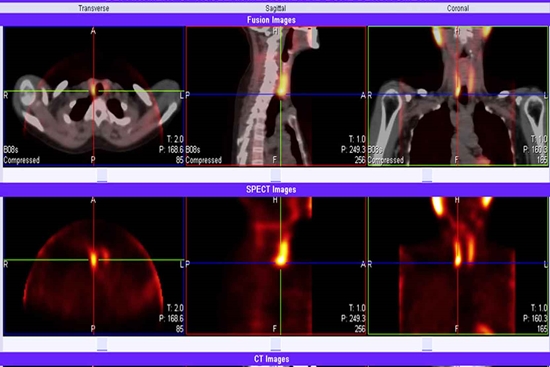

کنفرانس علمی تشخیص انواع تیروئید ها در بیمارستان شهدای تجریش برگزار شد

کنفرانس علمی پزشکی هسته ای برای تشخیص انواع تیروئیدیت ها با حضور اساتید مربوطه در بیمارستان شهدای تجریش برگزار شد.

در بخش آخر برنامه نیز دکتر قدسی راد عضو هیات علمی گروه پزشکی هسته ای به صورت کامل نماهای سینتی گرافی در بیماری های مختلف تیروئید را تشریح کرده و ضمن طرح کیس های مختلف ابعاد مختلف بحث را تبیین کرد.